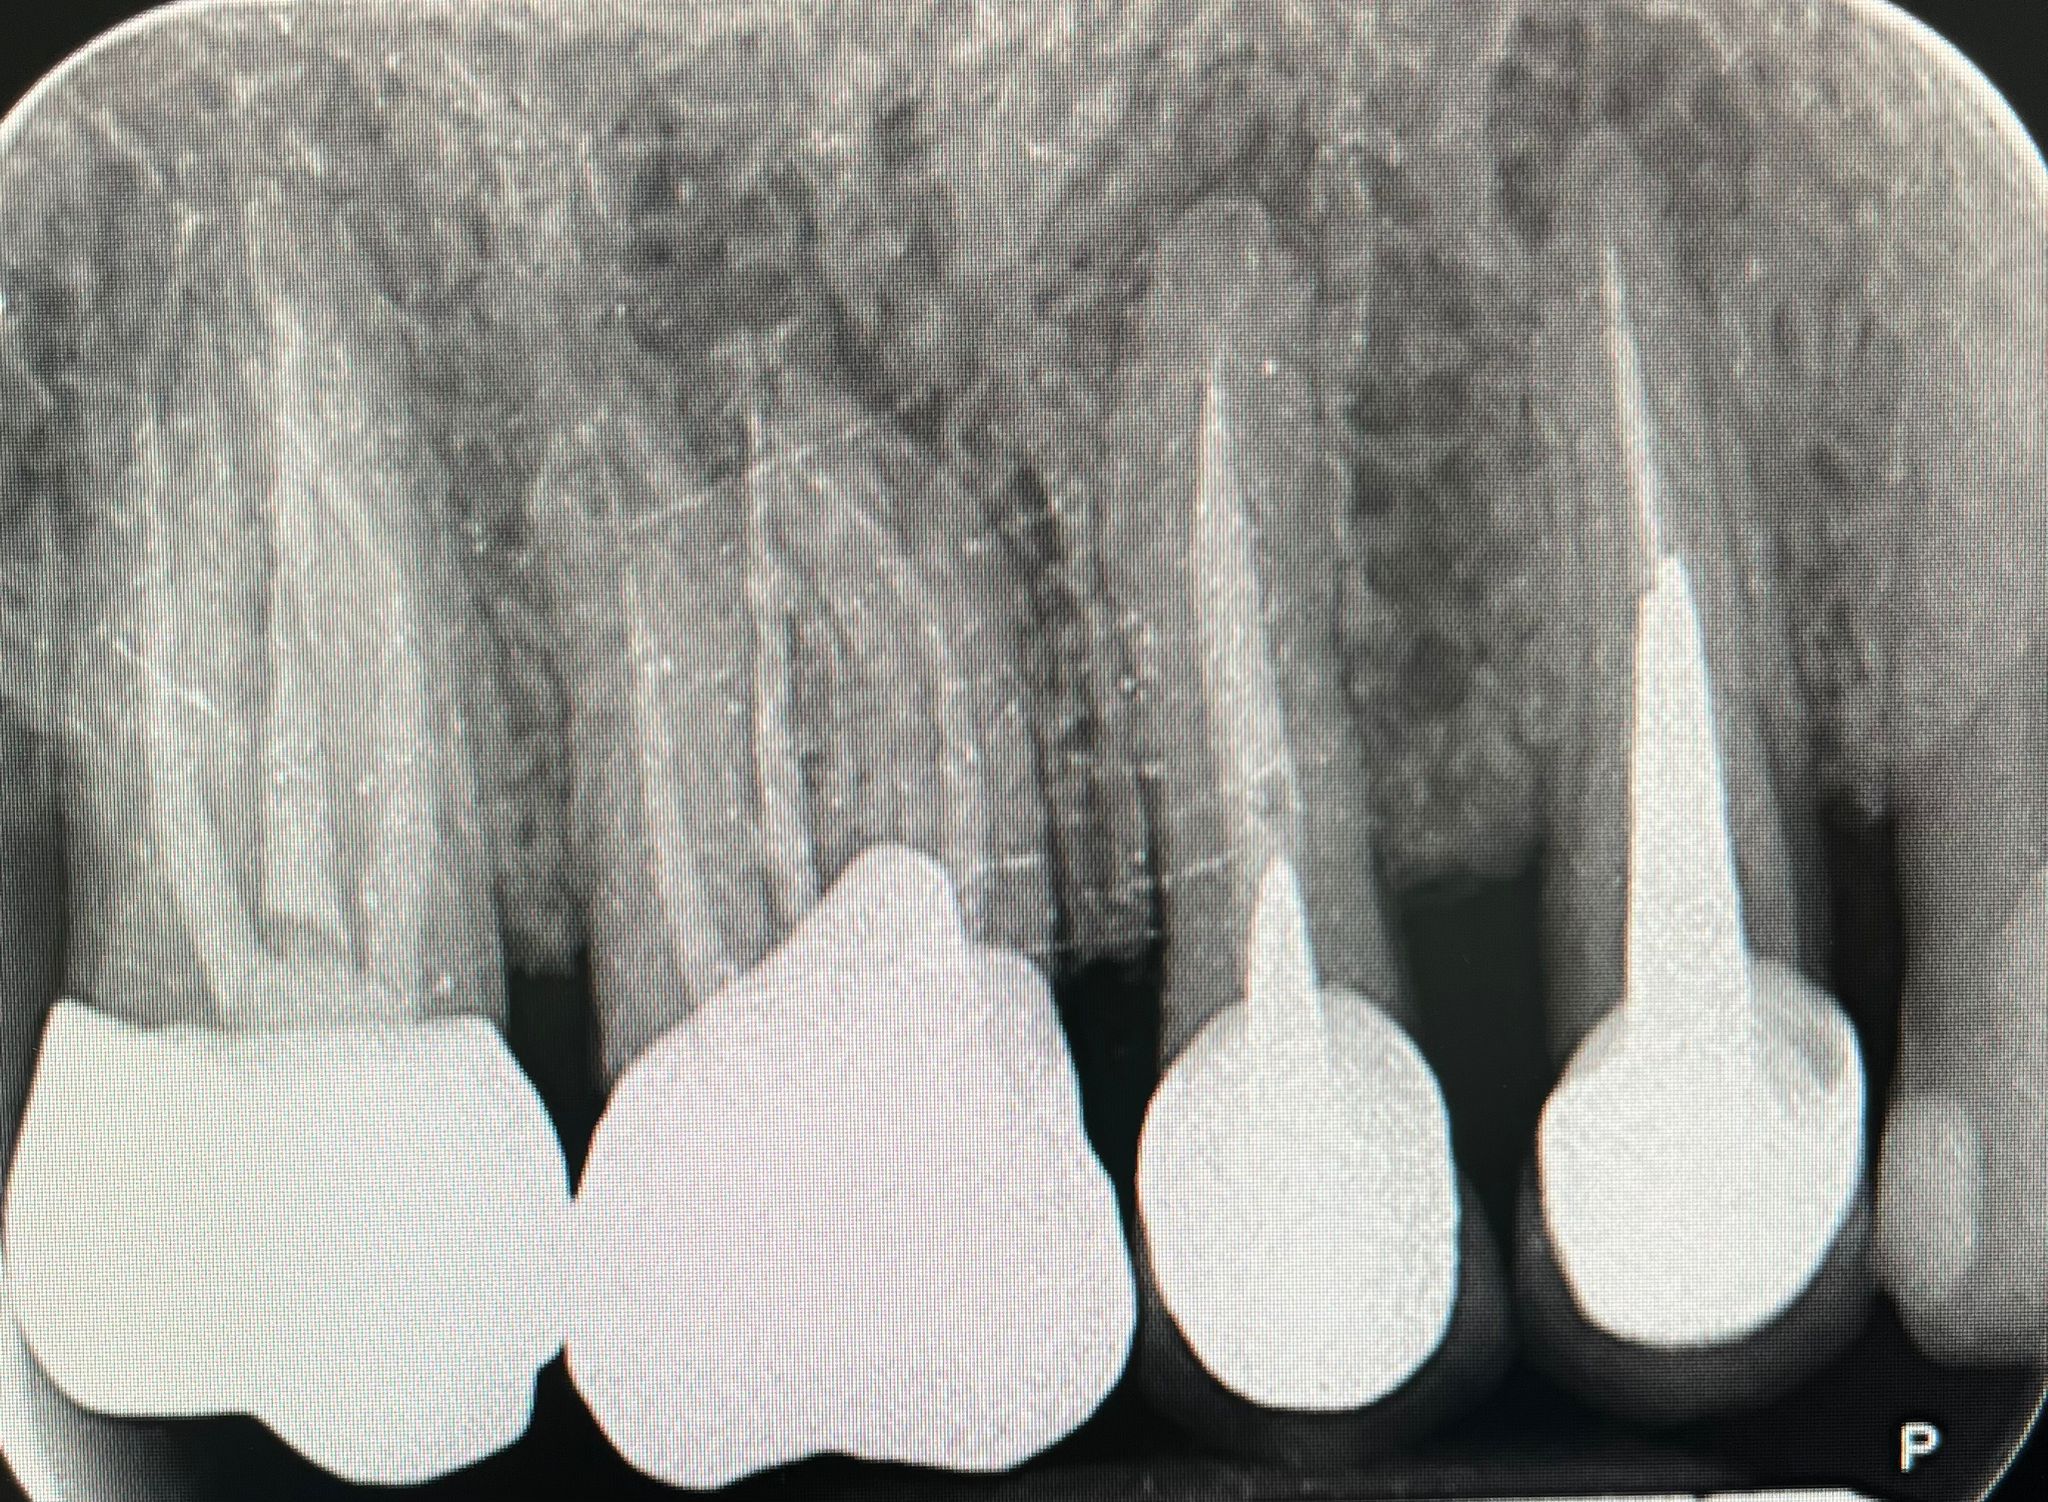

Presso lo Studio Dentistico Zambon siamo specializzati in trattamenti avanzati come il postestrattivo con carico immediato, un intervento innovativo che consente di sostituire i denti mancanti in modo rapido e sicuro, riducendo notevolmente il tempo di guarigione e il disagio per il paziente.

Grazie all’utilizzo della chirurgia guidata, siamo in grado di pianificare e realizzare impianti dentali con precisione, assicurando risultati eccellenti e duraturi.

Il trattamento postestrattivo con carico immediato è un protocollo che permette di inserire un impianto dentale subito dopo l’estrazione del dente naturale, evitando lunghi tempi di attesa tra l’estrazione e l’inserimento del nuovo dente. Questa soluzione si dimostra ideale per chi desidera ripristinare il sorriso e la funzionalità dei denti in tempi ridotti, evitando multiple sedute e massimizzando il comfort.

La chirurgia guidata è una tecnica avanzata che si avvale di tecnologie digitali per pianificare e simulare l’intervento in modo personalizzato. Con una scansione digitale 3D della bocca, il nostro team può posizionare gli impianti con estrema precisione, seguendo un percorso predefinito che riduce il margine d'errore. Questo approccio, unito al trattamento postestrattivo con carico immediato, offre diversi vantaggi: